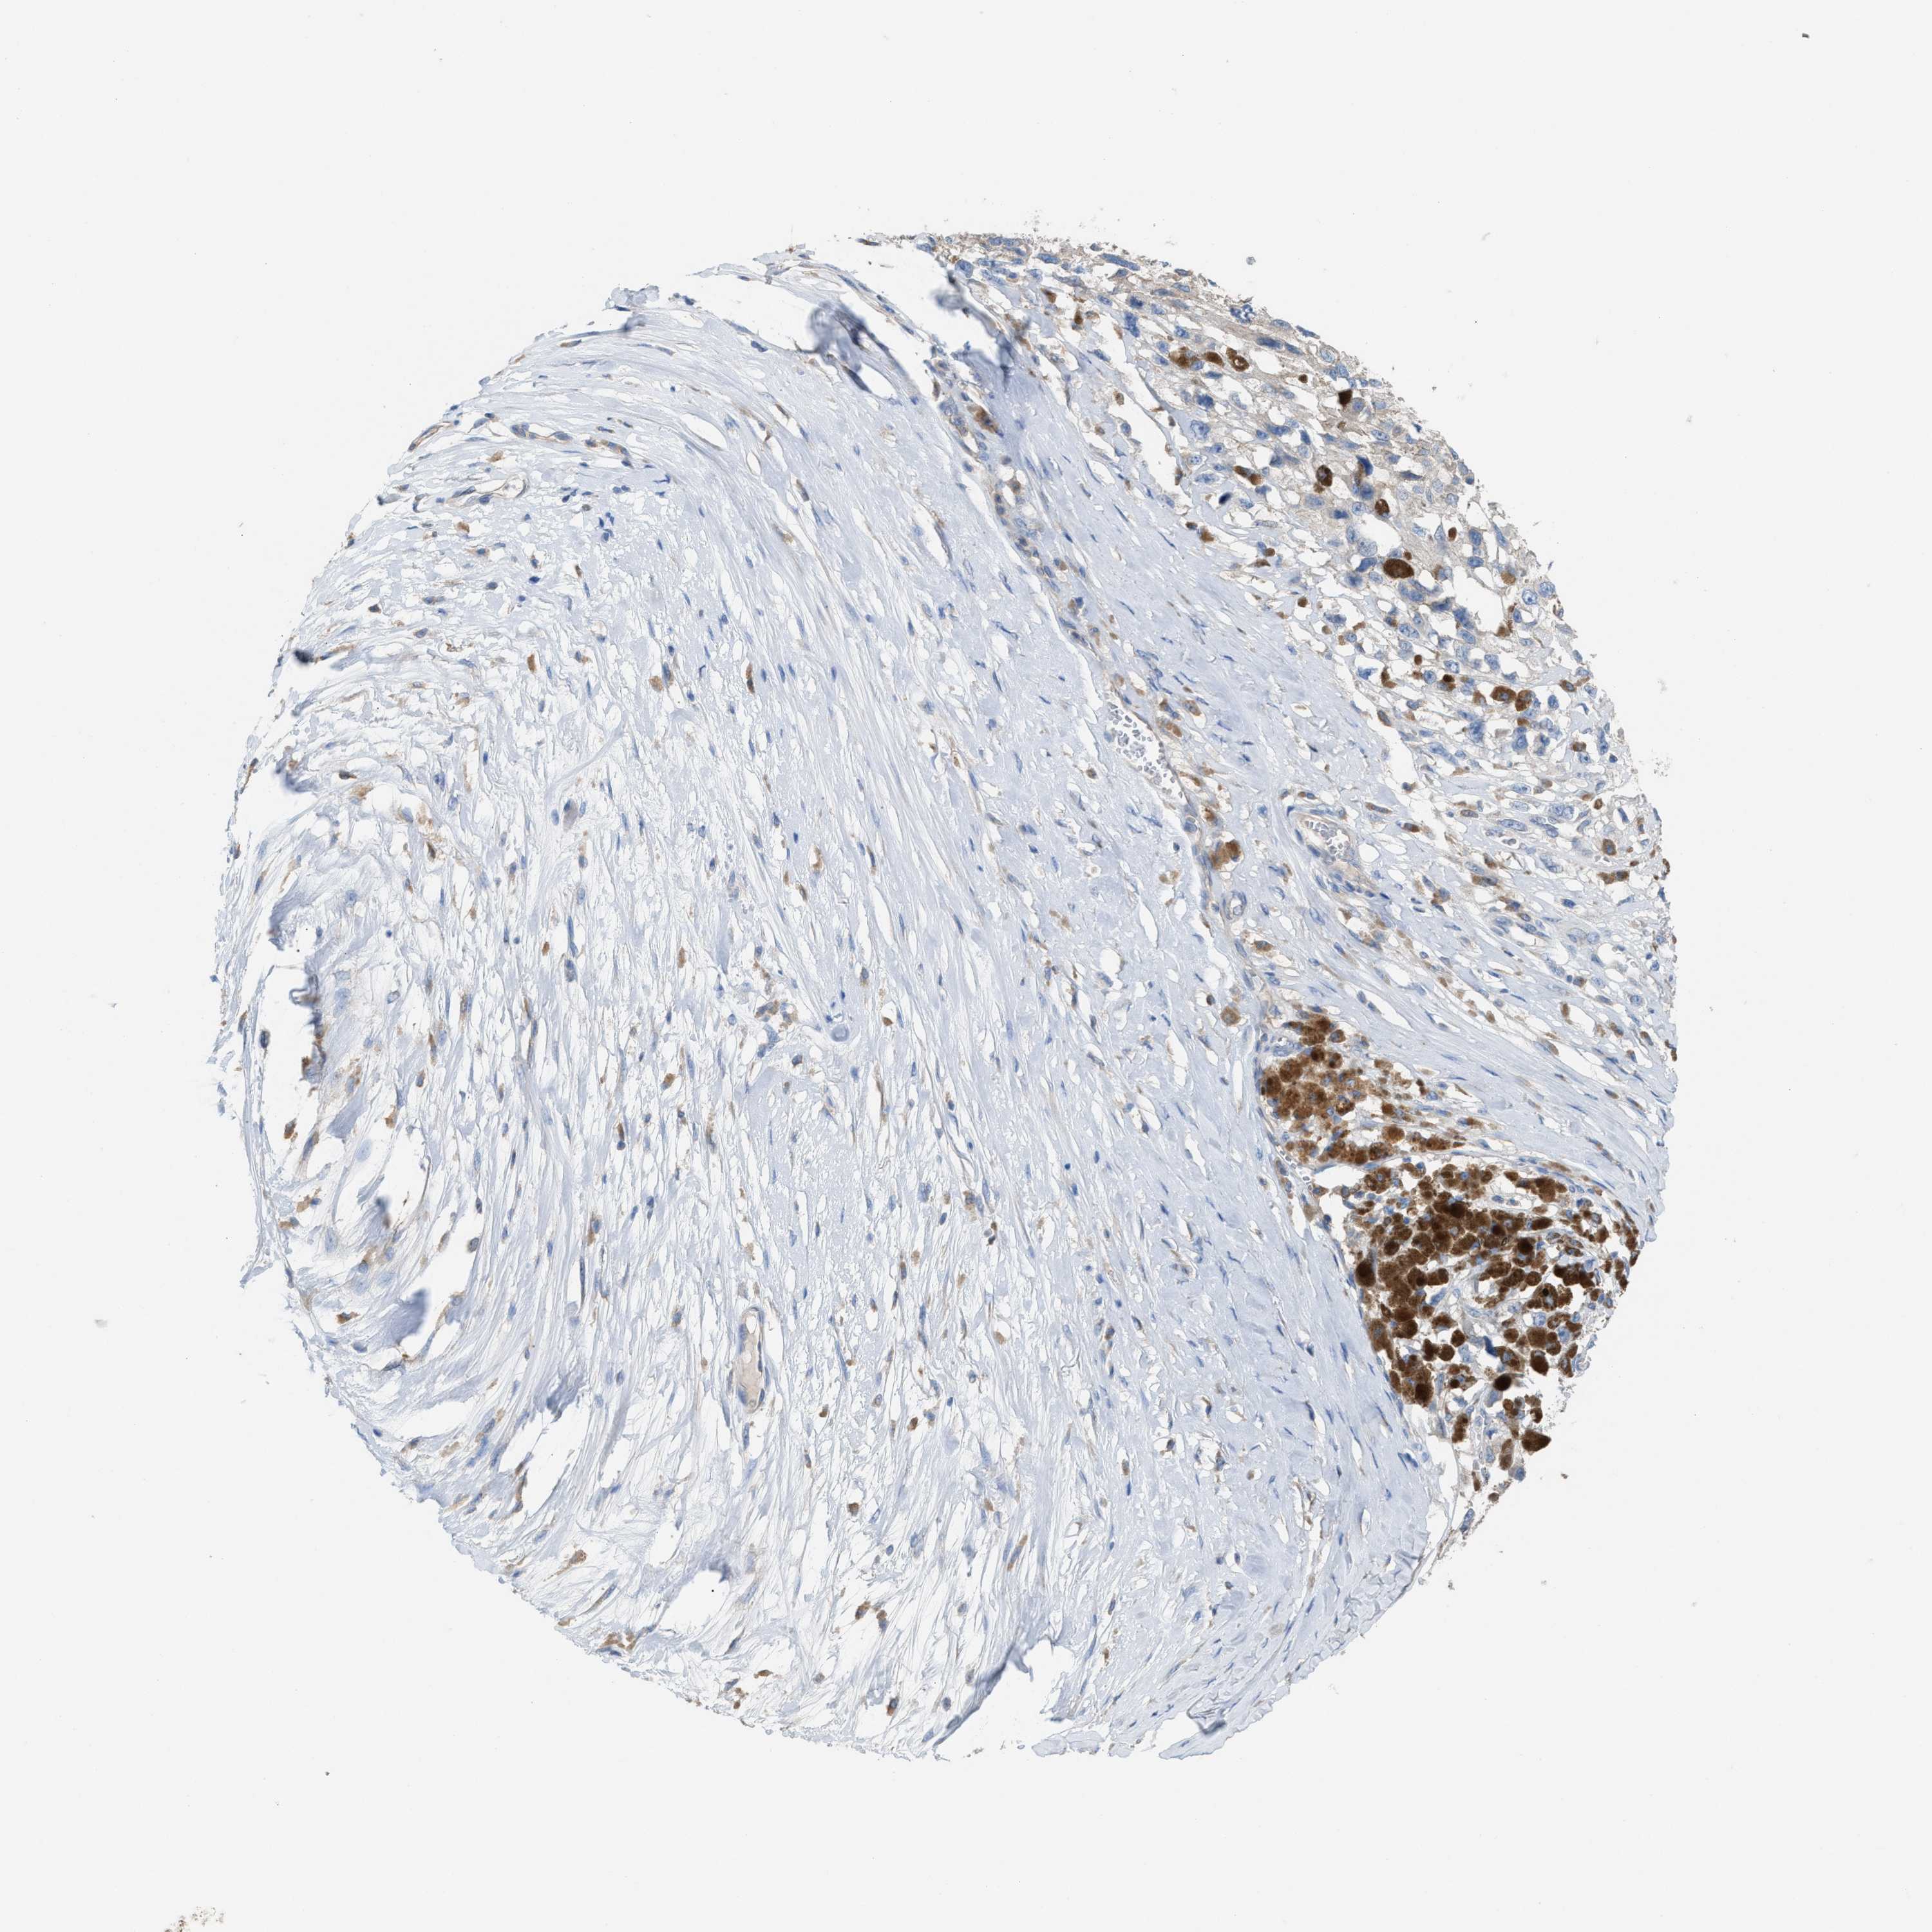

MELANOMA - Protein expressioni

A mouse-over function shows sample information and annotation data. Click on an image to view it in a full screen mode. Samples can be filtered based on level of antibody staining by selecting one or several of the following categories: high, medium, low and not detected. The assay and annotation is described here.

Note that samples used for immunohistochemistry by the Human Protein Atlas do not correspond to samples in the TCGA dataset.

Antibody stainingi

Antibody staining in the annotated cell types in the current human tissue is reported as not detected, low, medium, or high, based on conventional immunohistochemistry profiling in selected tissues. This score is based on the combination of the staining intensity and fraction of stained cells.

Each image is clickable and will lead to virtual microscopy that enables deeper exploration of all samples and also displays staining intensity scores, fraction scores and subcellular localization as well as patient and tissue information for each sample.

Antibody HPA021283

Antibody HPA021332

Staining

High

Medium

Low

Not detected

Intensity

Strong

Moderate

Weak

Negative

Quantity

>75%

75%-25%

<25%

None

Location

Nuclear

Cytoplasmic/membranous

Cytoplasmic/membranous,nuclear

Malignant melanoma, Metastatic site